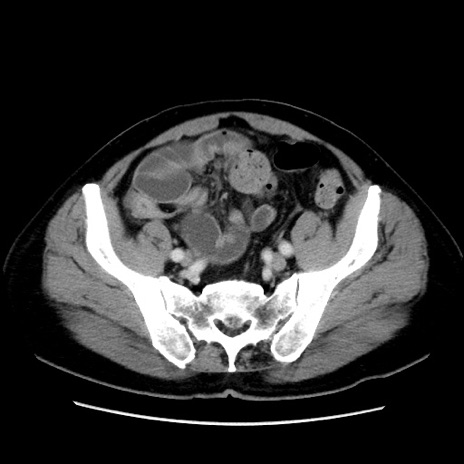

症例16(横断像)

【症例】 70歳代男性

【主訴】 腹痛、嘔吐

【現病歴】 約1ヶ月前より間欠的に腹痛と嘔吐あり、当院消化器内科を受診したところCTで多発する肝臓のLDAを指摘され、精査中であった。以降は消化器症状は安定していたが、2日前より嘔気と腹痛があり、同日より排便・排ガスが消失した。改善認めず、 本日、救急外来を受診した。

【既往歴】 大腸ポリープ切除後。

【身体所見】意識清明・会話良好、BT 36.3℃、BP 127/80mmHg、 P 80bpm、腹部:膨満あり、平坦・軟、上腹部正中および下腹部正中に圧痛あり、反跳痛なし、筋性防御なし。

【データ】WBC 7200、CRP 0.77